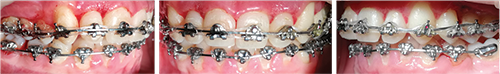

The case presented here is a 15-year-old male with severely crowded dentition and both maxillary canines completely blocked out of the dental arch. He had a Class II occlusion on the right, a Class I relation on the left, and a normal overbite/overjet relationship of the incisors (Fig. 1).

Fig. 1: Initial records